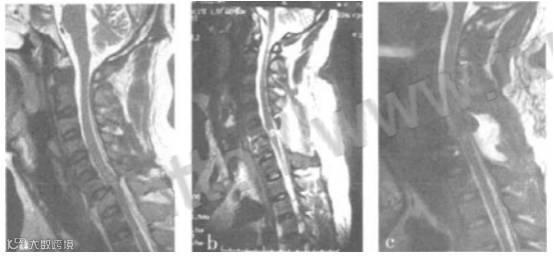

典型病例:患者,男,24岁,因“骨折脱位、颈脊髓损伤、四肢瘫术后”1个月(2008年10月)入院行干细胞治疗。入院时双下肢肌力0级。不能自主二便。术后1个月出现双足拇趾主动轻微活动。共行3次干细胞治疗,1年后随访已经可以扶物站立,并能自主控制二便。术后3个月复查MRI显示脊髓实质内出血及水肿明显吸收。

不同时期MRI表现

a.术前MRI表现; b.减压术后1个月; c.细胞移植术后3个月